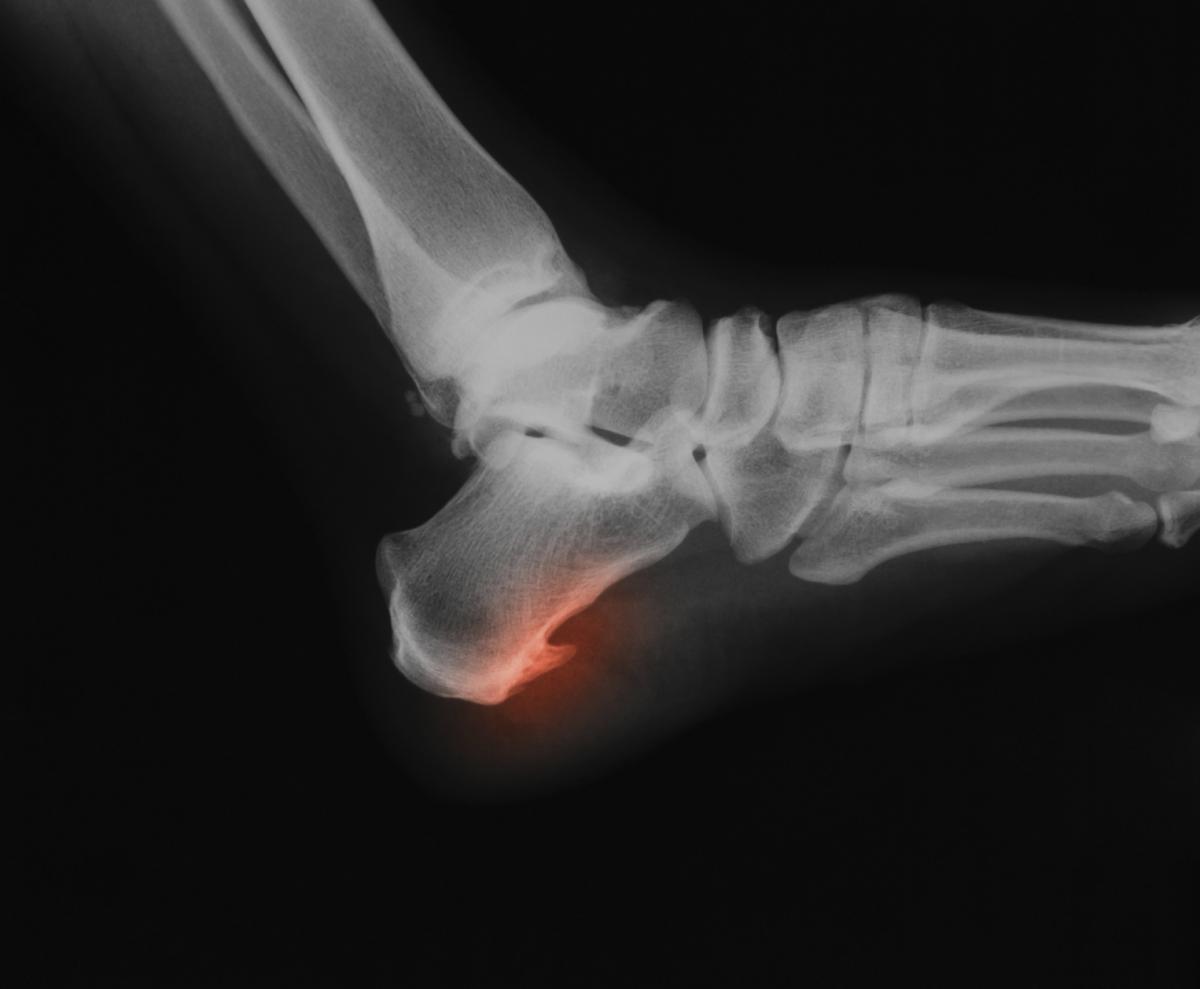

Un espolón calcáneo se produce cuando se genera una formación ósea en la zona inferior del hueso del talón, una condición dolorosa y altamente molesta que suele ser producto de una fascitis plantar no atendida. Debido a este cuadro y a las molestias que ocasiona en el paciente, la intervención de un podólogo es fundamental para garantizar una adecuada recuperación, proceso que puede ser largo.

La inflamación será la manera que tiene nuestro cuerpo para proteger la zona sobrecargada, lo que se conoce como fascitis plantar. Si esta condición no se atiende, el cuerpo acabará por generar una calcificación en la zona, es decir una pequeña formación ósea, lo que ocasionará dolor y molestias mucho más intensas e importantes, llegando incluso a afectar la capacidad de caminar distancias medias e impactando la realización de actividades cotidianas.

En el caso de que creas que se ha formado un espolón calcáneo en tu pie, lo primero que deberás hacer será visitar a un médico o especialista para que te examine y confirme el diagnóstico.